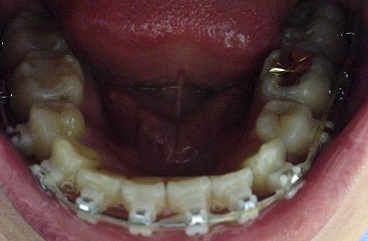

사진기준으로 오른쪽부분에 스크류를 심고왔어요 스크류를 더불어 당기는 힘의 균형을 맞추어 준답니다.

중간중간 제가 아픈지도 확인하시면서 사진 보시는것처럼

새로운 스크류 자리잡기를 하고왔습니다.